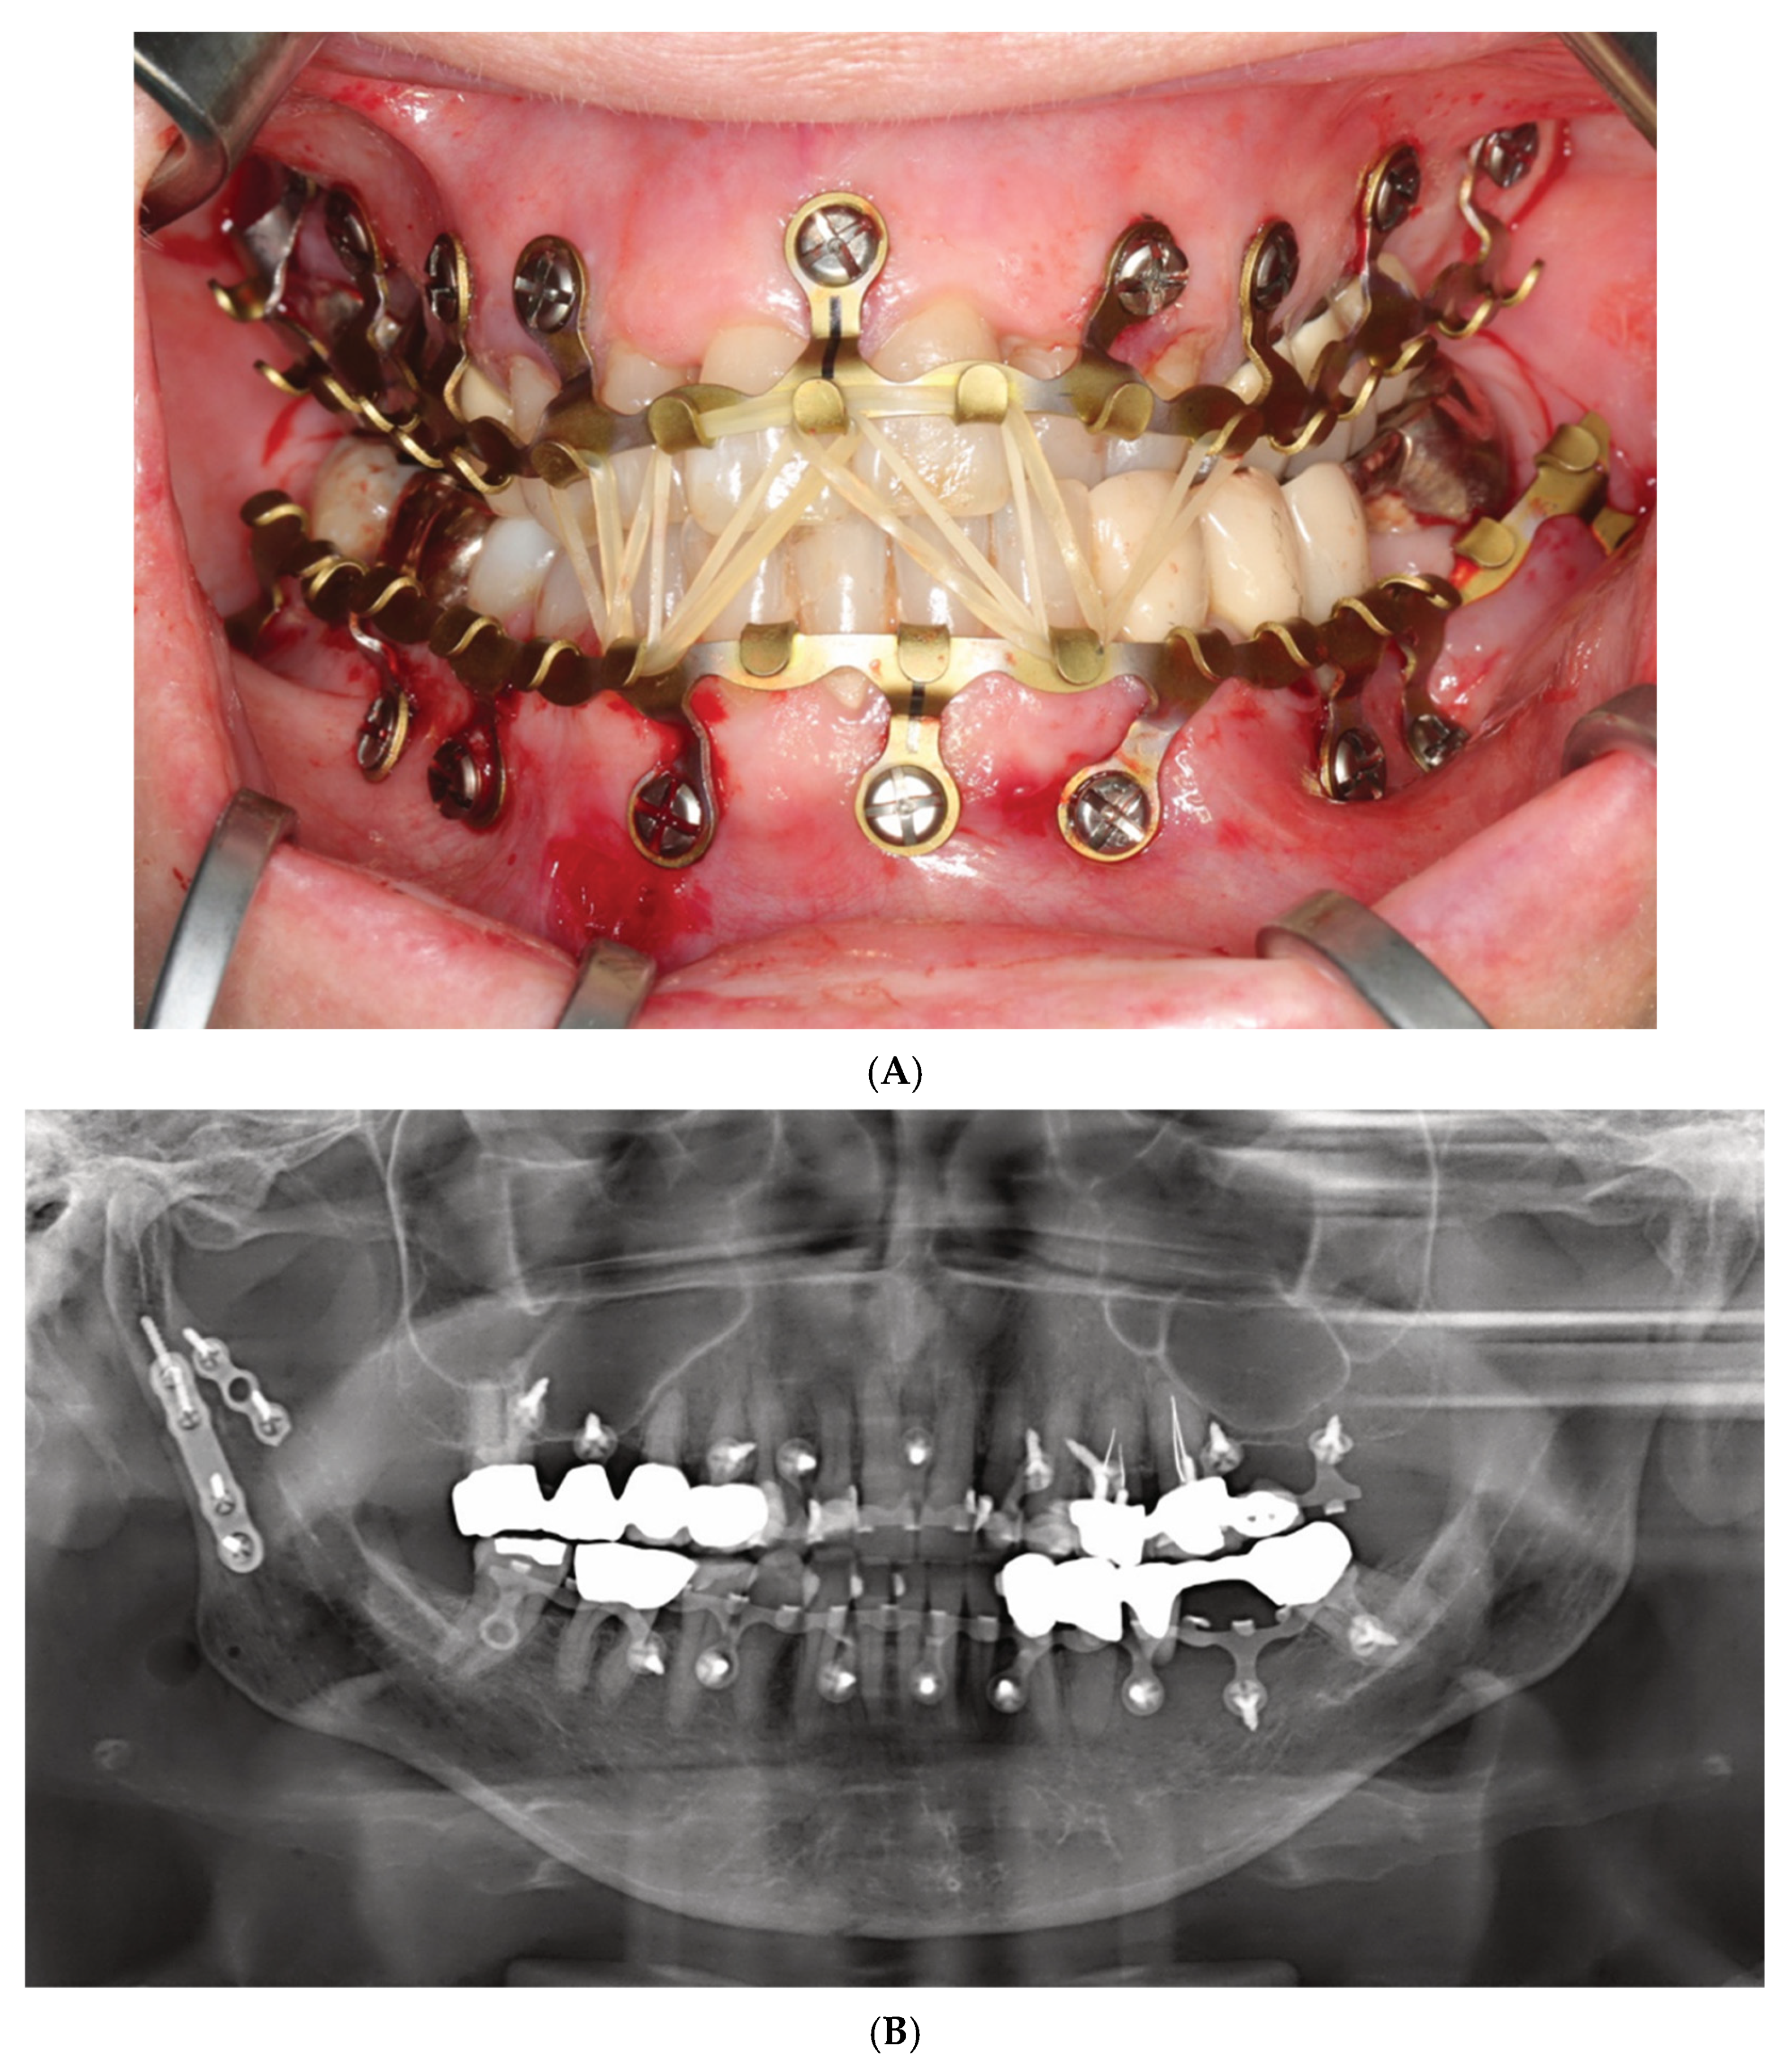

Figure 4.

(A) Clinical case example—intraoperative view of Zimmer Biomet OmniMax MMF devices divided into 4 segments for treatment of a triple mandibular fracture—bilateral condylar base and symphyseal midline. A dental splint (Titanium Trauma Splint, Medartis, Basel, Switzerland) resin bonded (acid etching technique) to the outer surfaces of the teeth of the anterior maxillary arch supports the repositioned medial upper incisors. The two maxillary segments represent the shortest possible plate variant consisting of a single mounting tab containing two slot apertures, with 2.0 four-hole miniplate visible in open anterior vestibulum approach. Of note: the standoff mechanism has been implemented for all screws—annular screw grooves fully seated in the slots. (B) Previous case cont’d. Postoperative panoramic X-ray after placement of OmniMax arch bars, ORIF—via transoral vestibular and preauricular transparotid approaches. Miniplate fixation of the condylar base fractures. Four-hole superior border (tension band) miniplate fixation in combination with a six-hole 2.4 inferior border plate. The arch bar retaining screws appear inserted correctly in the interradicular spaces. Source/origin: Photograph collection—C.P. Cornelius.